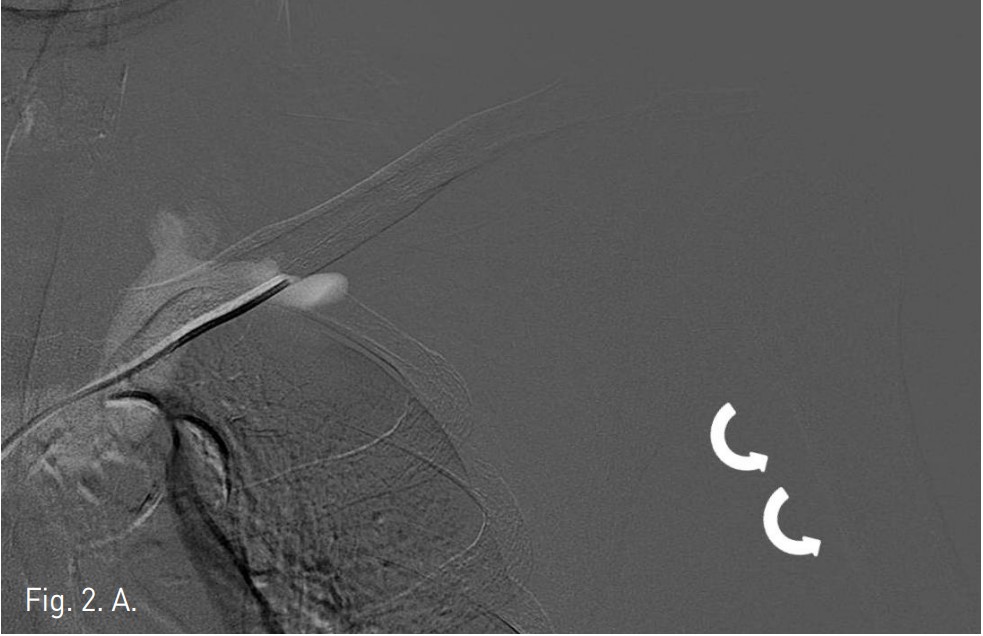

CT에서 left subclavian vein이 subclavius muscle과 anterior scalene muscle 사이에서 좁아져 있는 것이 관찰된다(Fig. 1). 팔을 내리고 시행한 venogram에서 subclavian vein이 막혀 있고 wire가 통과하지 않았으나(Fig. 2A), 팔을 머리 위로 올리고 시행한 venogram에서 subclavian vein의 distal portion이 관찰되고 catheter가 통과되었다(Fig. 2B).

Fig. 2. A

Fig. 2. A. Initial subclavian venogram with the arms held to the sides(curved arrows) shows total occlusion of subclavian van.